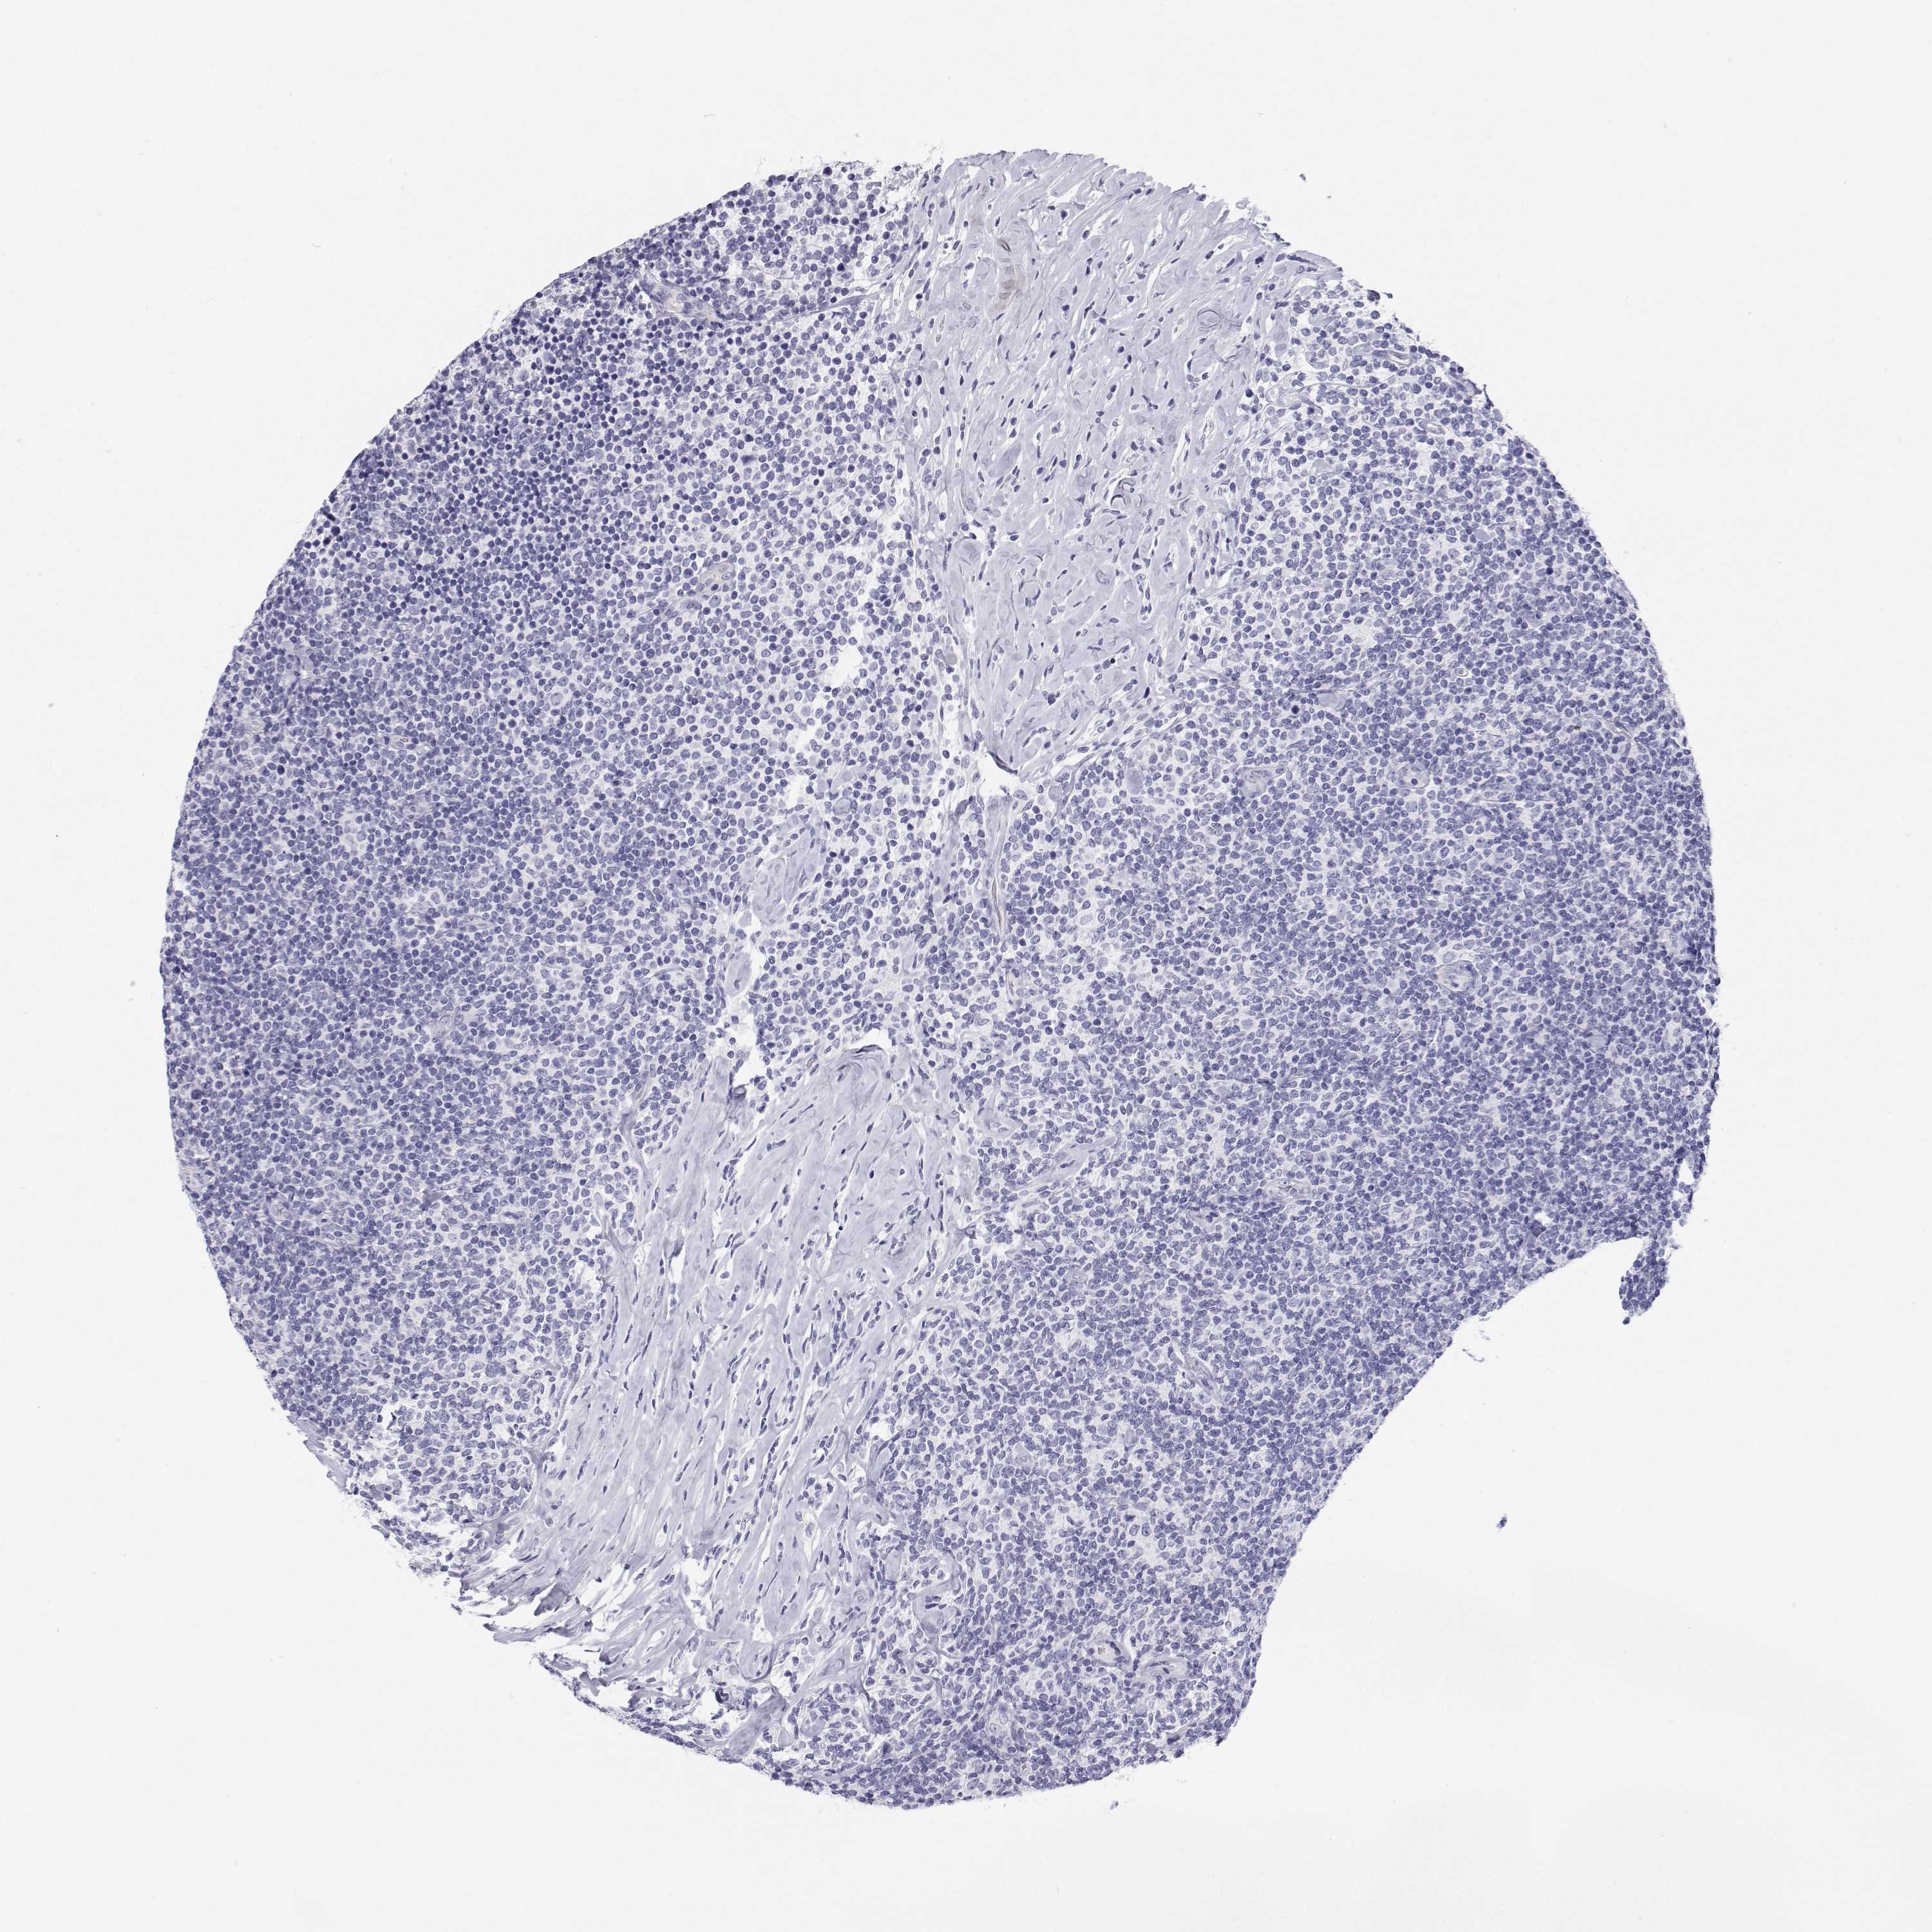

CANCER LYMPHOMA Show tissue menu

LYMPHOMA - Protein expressioni

A mouse-over function shows sample information and annotation data. Click on an image to view it in a full screen mode. Samples can be filtered based on level of antibody staining by selecting one or several of the following categories: high, medium, low and not detected. The assay and annotation is described here.

Each image is clickable and will lead to virtual microscopy that enables deeper exploration of all samples and also displays staining intensity scores, fraction scores and subcellular localization as well as patient and tissue information for each sample.

Antibody HPA038285

Antibody HPA058310

Hodgkin's disease, NOS

Malignant lymphoma, non-Hodgkin's type, High grade

Malignant lymphoma, non-Hodgkin's type, Low grade